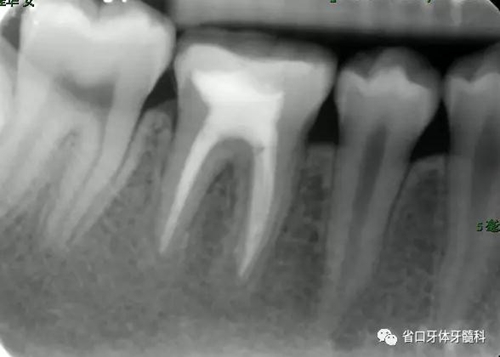

圖4 根管治療術(shù)后17個(gè)月:根分叉和根尖低密度影基本消失